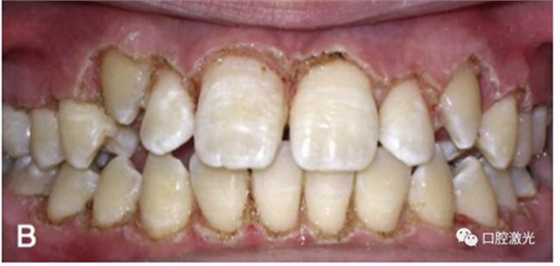

有時,會遇到一些口腔衛(wèi)生問題比較嚴重的患者,從而導致牙齦發(fā)炎而腫大。通過改善口腔衛(wèi)生環(huán)境,炎癥可以得到緩解,但增生的牙齦不一定都可以完全恢復。下圖的患者就存在口腔牙齦肥厚問題,同時左上部犬牙存在部分萌出的問題,右上部犬牙存在未萌出問題,這些問題都妨礙了托槽的粘接。因此,實施了全口腔的牙齦整形手術(shù)。去除了多余的牙齦組織,增加了犬牙的暴露面積,從而使托槽的粘接更為便利,同時也提升了患者保持口腔衛(wèi)生的狀況。

治療前

激光牙齦整形后即刻

激光治療當天粘接托槽

6周后效果